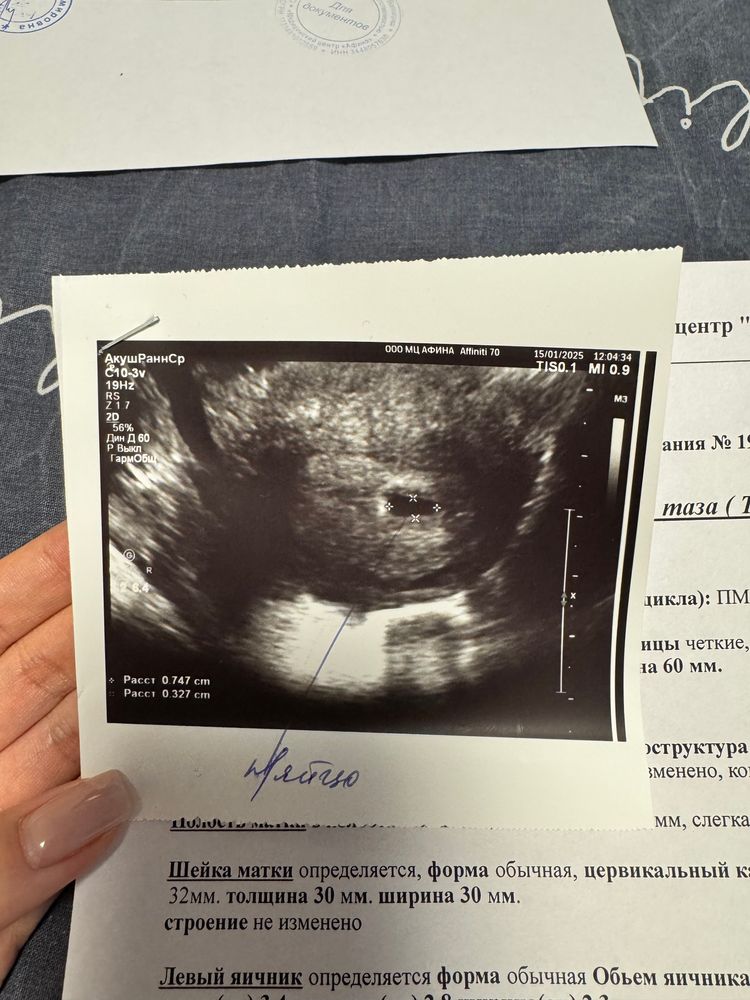

Первое УЗИ было на сроке 4 недели 5 дней, нашли ПЯ 13 мм (еще тогда смутило, что большое намеряли), желт. м 2мм.

Второе УЗИ в другой клинике на сроке 5 недель 5 дней, СВД 12 мм, ктр 3,1 мм, желт. м 3,6 м